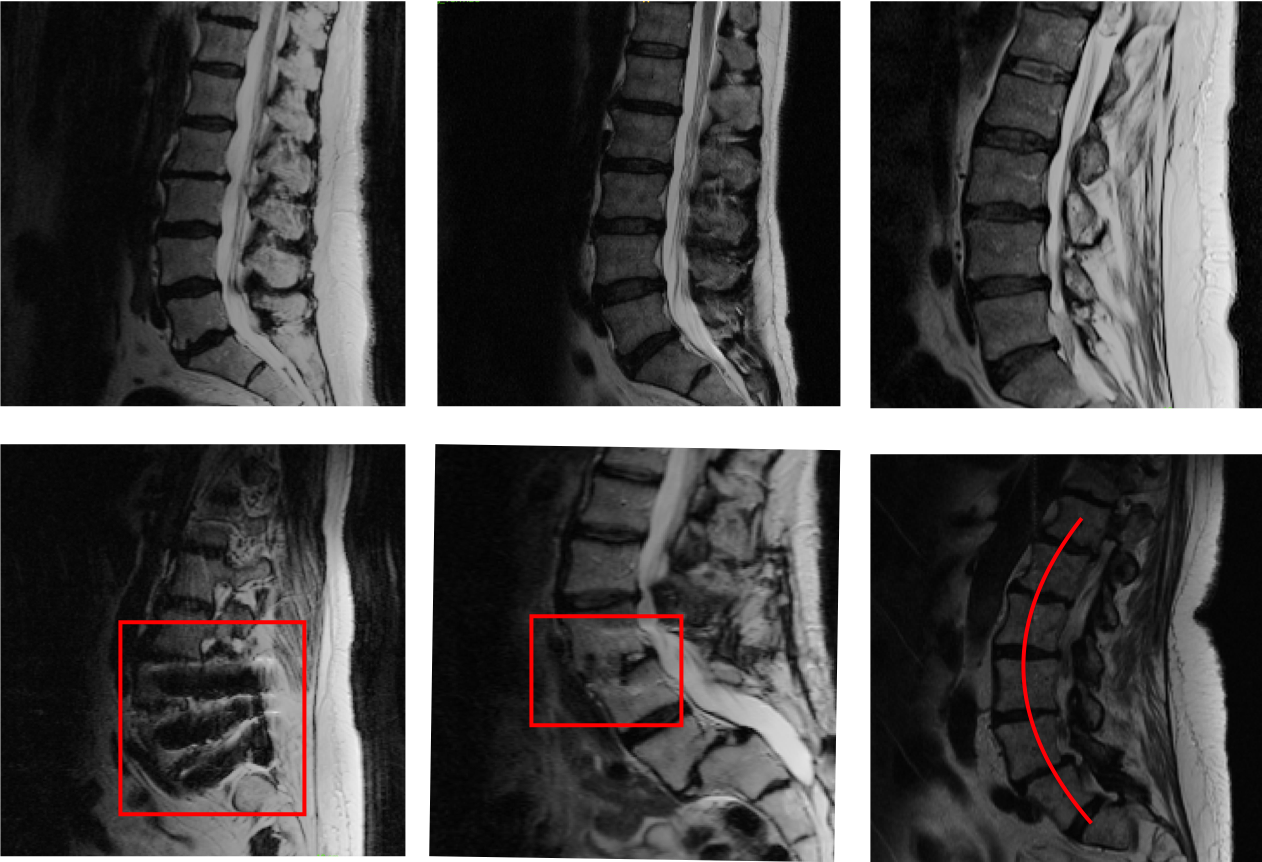

III-B Eigenrank for intervertebral disk segmentation

To further convince the reader of the value of Eigenrank, we ran the aforementioned experiments in a separate dataset where the objective was automatically segmenting disks on lumbar spine MR images. The full dataset contained 103 MR scans. Inter-vertebral disks were segmented manually using techniques similar to spinal canals. We ran Eigenrank using same network and parameters as the previous experiment. A sample of images selected by Eigenrank are shown in figure 4. Standard deviations and means of Dice scores associated with data subset selection on left-out data are shown in table IV. Dice scores on validation data derived by eliminating ‘cases chosen’ by each specific algorithm iteratively are shown in table V. Failure prediction results are shown in VI.

Refer to caption

Figure 4: Top Row Randomly selected subjects Bottom Row Subjects selected by the first iteration of the Eigenrank